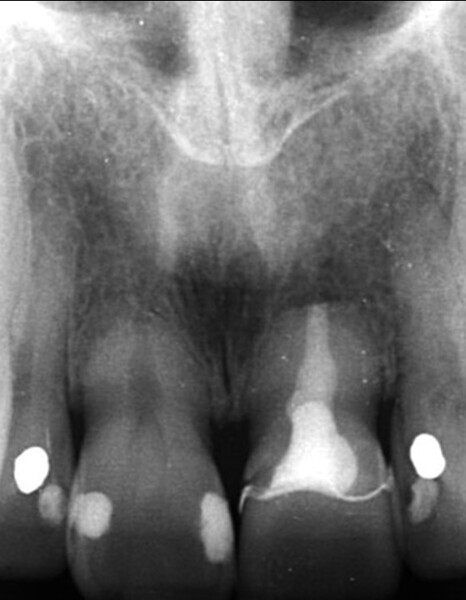

Fig. 3: Pre-op periapical radiograph.